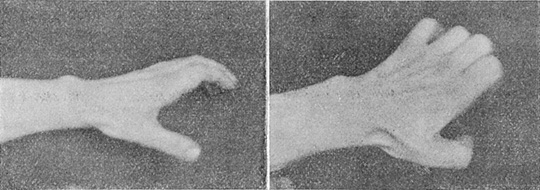

Ved det herværende glasverk foregaar slipningen av en del finere glasvarer paa den maate, at vedkommende glassliper maa hvile albuen paa en bordplate, mens han holder glasgjenstanden, som skal slipes, op mot slipeindretningen. Nervus ulnaris utsættes derved i albuleddet for et tryk; nerven lider derved i sin ernæring, og dens funktion hemmes, saaledes at der fremkommer en affektion, der i sin mest utprægede grad gir haanden den saakaldte «klostilling». (Se hosstaaende fotografier fra en arbeiders haand.)

Det gaar nemlig ut over mm. interossei. Disse skal bøie metakarpofalangealleddene og strække interfalangealleddene. Lammes n. ulnaris, eller lider den i sin funktion, er utførelsen av begge disse bevægelser ikke mulig. Bortfalder interosseis bevægelser, vinder antagonisterne saadan overhaand, at fingrene faar en eiendommelig stilling som er motsat den, de faar igjennem kontraktionen av interosserne. Der blir bøiestilling av interfalangealleddene, og antagonisternes indflydelse paa metakarpofalangealleddene fører efterhaanden derhen, at der indtrær en dorsalfleksion ved de siste led – en deformitet, som ikke er mulig under normale forhold. Kombinationen av bøining i interfalangealleddene og dorsalfleksionen i metakarpolfalangealleddene gir da haanden den karakteristiske stilling, som gir den en viss likhet med en fugleklo.